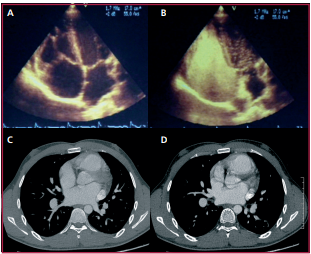

Integración diagnóstica en la comunicación interauricular

IMÁGENES EN CARDIOLOGÍA